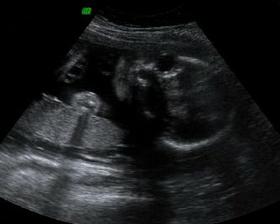

24.2.2010 - Velký utz!!! - ČEKÁME CHLAPEČKA - BUDE TO DAVÍDEK!!!!

Dle utz 21+3tt, vše jak má být, Davídek je naprosto zdravé miminko 🙂